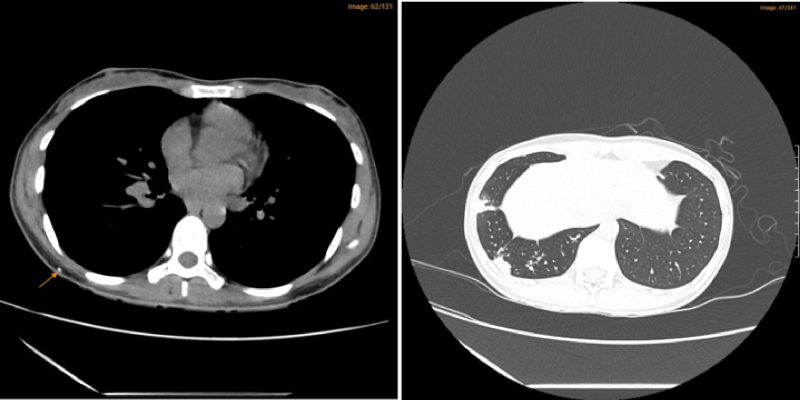

-         Hệ thống máy chẩn đoán hình ảnh hiện đại, hỗ trợ tốt nhất quá trình thăm khám, điều trị và theo dõi bệnh như X-quang, siêu âm, nội soi, MRI, CT Scan,... được nhập khẩu từ Hoa Kỳ, Đức, Thụy Sĩ.